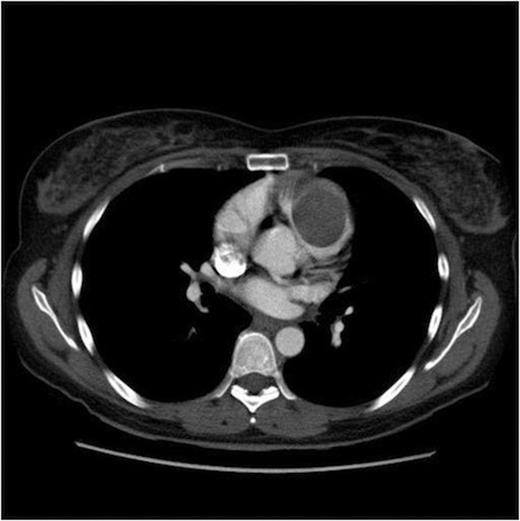

Echocardiography revealed a very large lobulated heterogenous mass in the right ventricular apex. A further mass or extension of this was also seen in the right ventricular outflow tract. This extension was mobile and had a homogenous texture. MRI and CT Thorax (Figures 1 & 2) demonstrated a 4.1cm x 9cm x 4.1cm lobulated mass within the right ventricle, obstructing the right ventricular outflow tract.